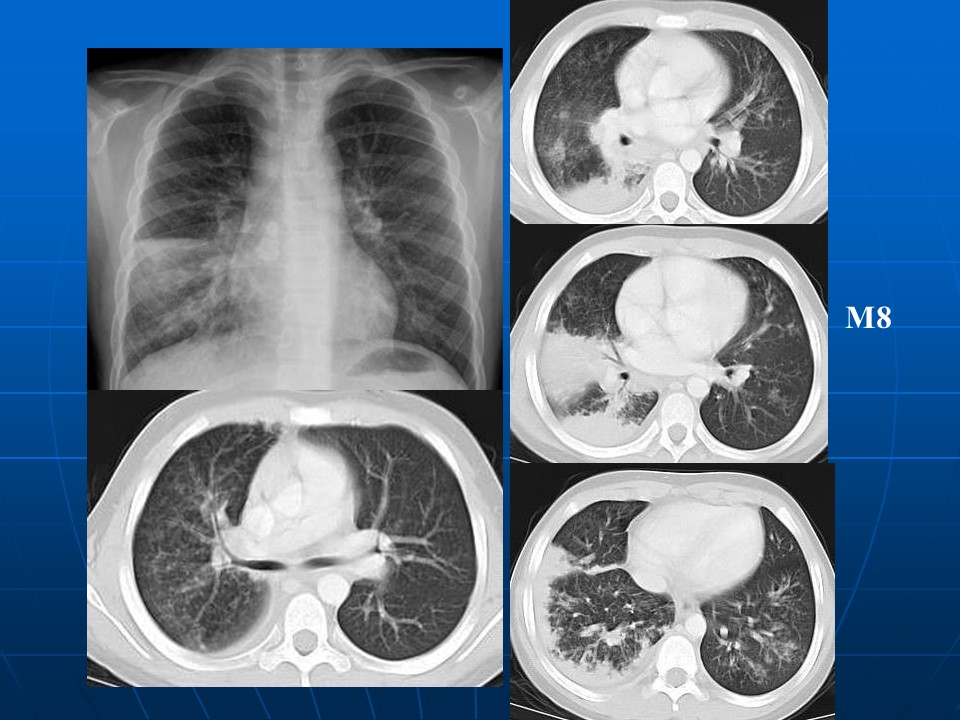

如何在影像上判断新冠病毒肺部感染是否好转